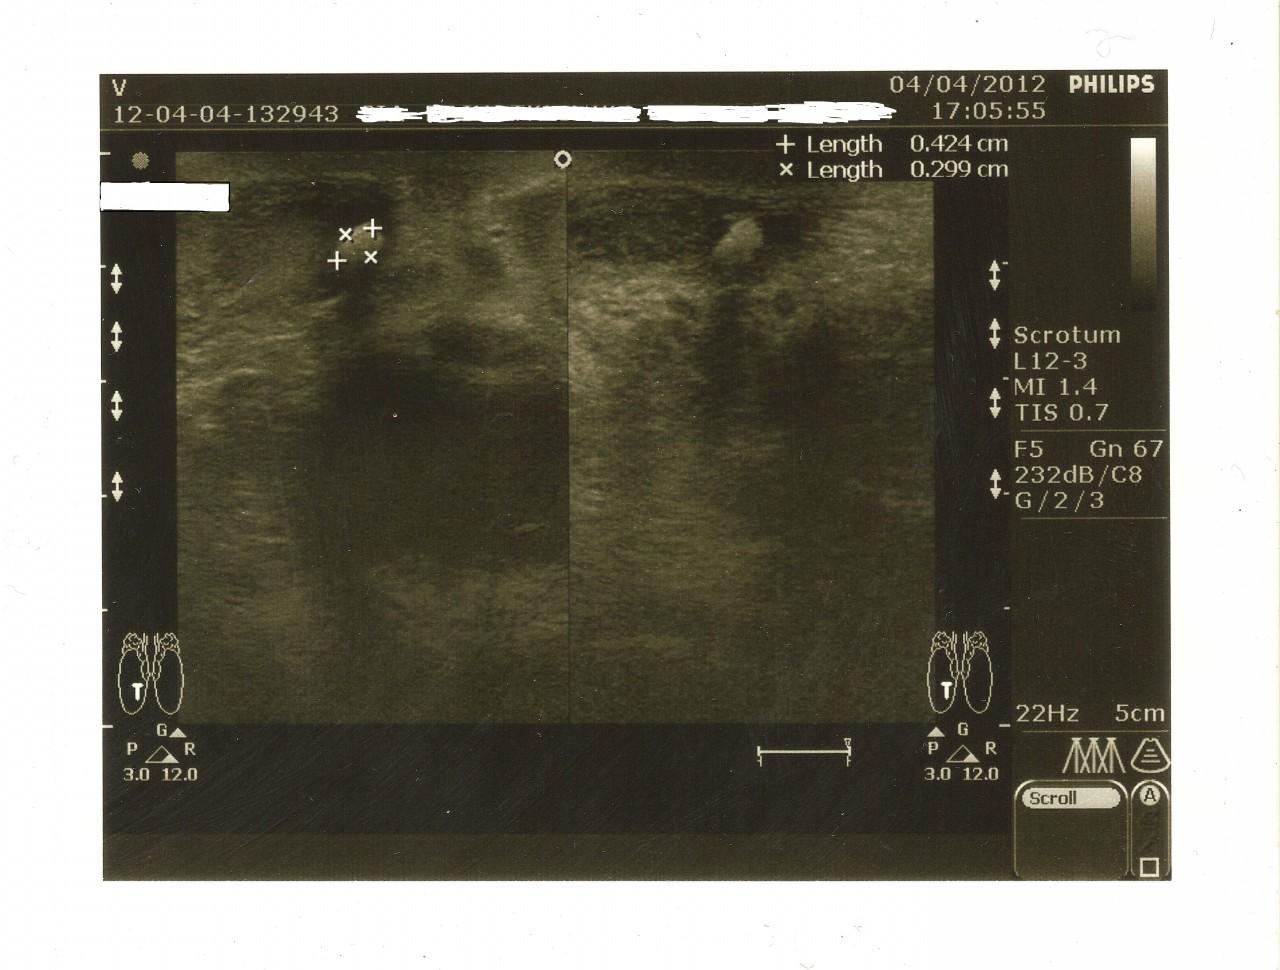

сегодня сделал узи,врачь толком ни чего не объяснила.результат узи правое левое яичко 40х25 мм,в праой половине мошонки образование 4.2х3 мм подвижное,ну и всё.боли есть,самого яичка и оброзования отдаёт в ногу чутка и в правой бок, врачь говорит всё норм ну я хочу выяснить что это может быть!!!!к урологу не успеваю завтра к командировку и на долга ,помагите пожалуста